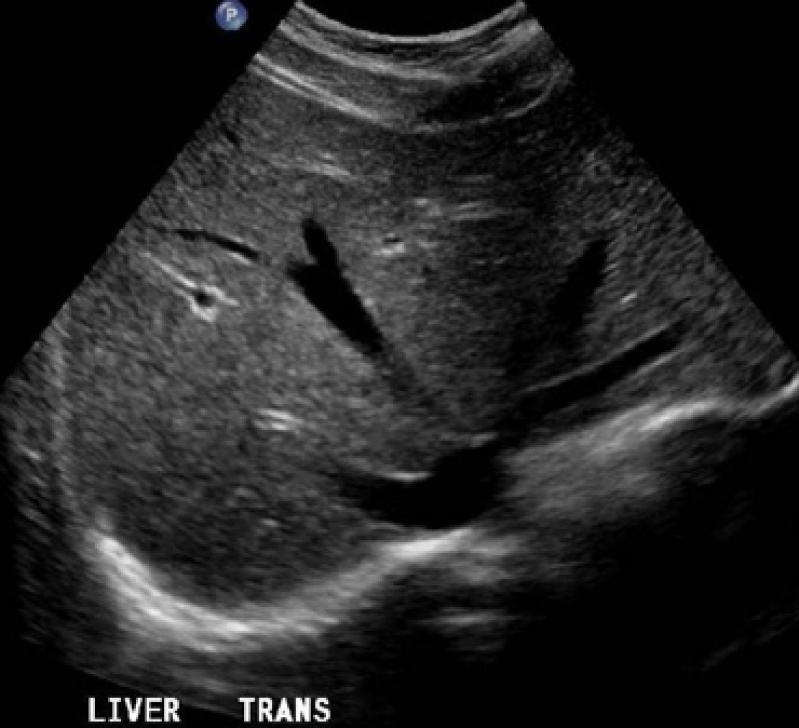

Com um exame de tomografia é possível captar imagens em tons de cinza de determinadas partes do corpo ou de algum órgão do paciente. A preparação para realizar o exame de tomografia é simples e consta apenas de cuidados anti-alérgicos.